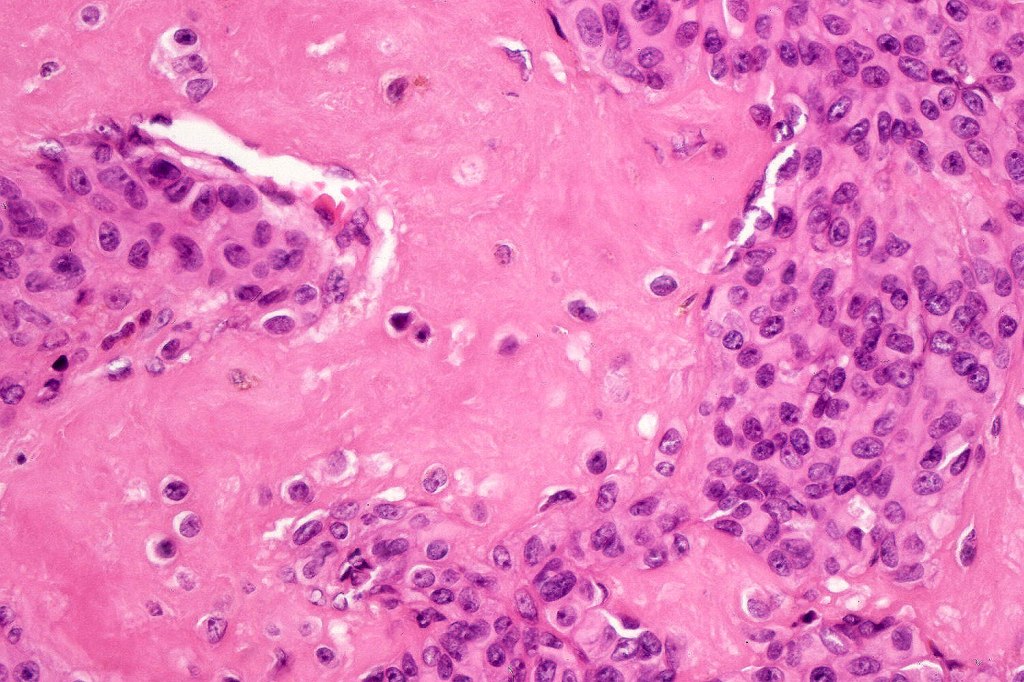

•It is hypercellular and most often composed of epithelioid cells showing little pleomorphism & only occasional mitoses

•Nuleoli are small

•Intracytoplasmic pseudo-inclusions

•The constituent cells are generally larger than the adjacent nevus cells

•Some examples show more marked pleomorphism with prominent nucleoli and increased mitotic activity but abnormal mitoses are not a feature. These are not associated with any sinister biological potential